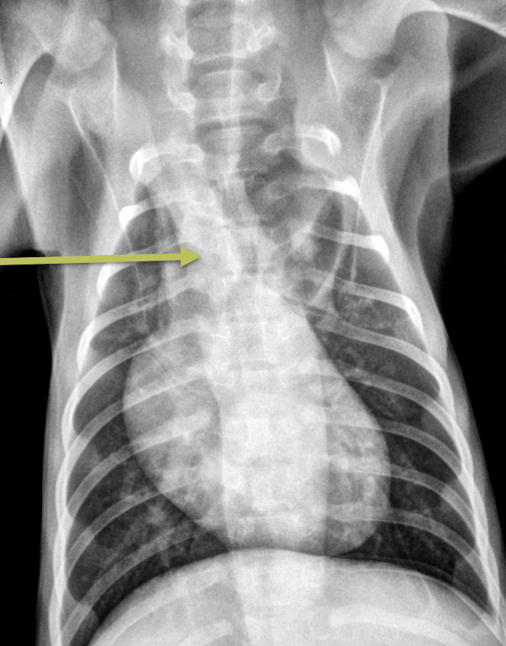

11

Esophageal dilation

Arrow = tracheal stripe